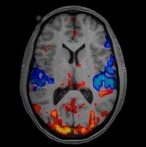

Se puede ver el dolor ? Pues sí

La evaluación del dolor a través de la Resonancia Magnética es el Futuro , la Dra Catalá ( Anestesióloga y Experta en Dolor ) en Barcelona es pionera de una investigación seria e interesante que ya recoge sus frutos y nos ilusiona .